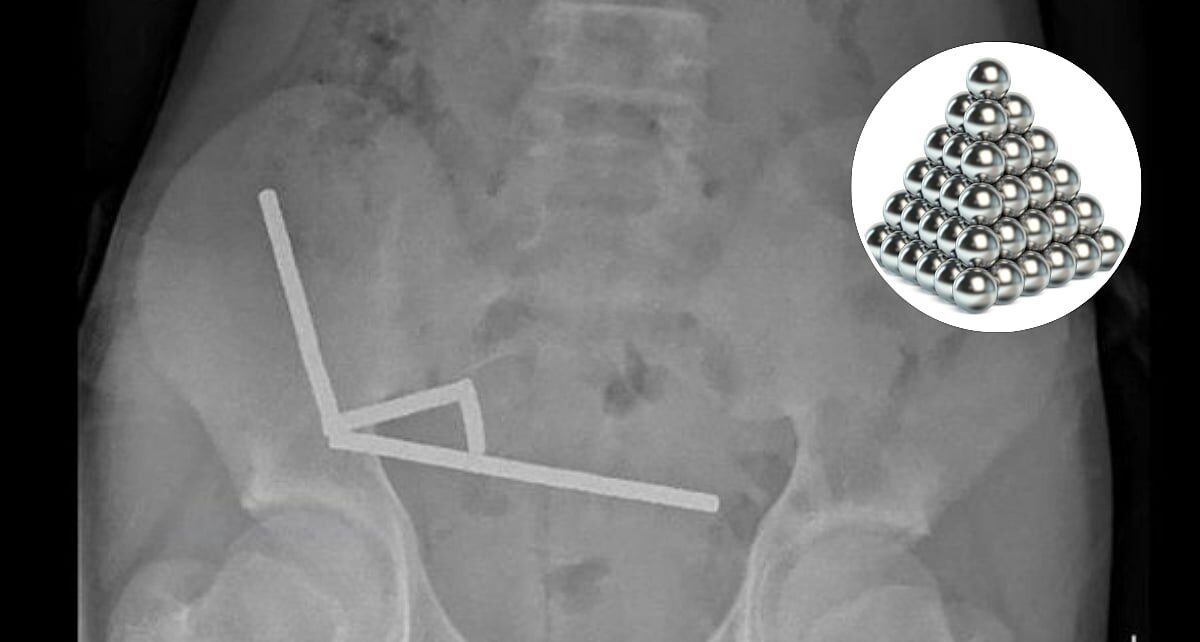

ന്യൂസിലാൻഡ്: ഇന്റർനെറ്റിലെ ഒരു ഇ-കൊമേഴ്സ് സൈറ്റില്നിന്ന് വാങ്ങിയ ഡസൻ കണക്കിന് ശക്തിയേറിയ കാന്തങ്ങൾ വിഴുങ്ങി 13 വയസ്സുകാരന്. വയറുവേദനയുമായി ആശുപത്രിയിൽ പ്രവേശിപ്പിച്ച 13 വയസ്സുകാരന് സങ്കീർണ്ണമായ ശസ്ത്രക്രിയ നടത്തേണ്ടിവന്നുവെന്നുമാത്രമല്ല, എല്ലാ കാന്തങ്ങളും പുറത്തെടുക്കാൻ ഡോക്ടർമാർക്ക് കുട്ടിയുടെ കുടലിന്റെ ഒരു ഭാഗം നീക്കം ചെയ്യേണ്ടിയും വന്നു.

ചെറിയ, ശക്തമായ കാന്തങ്ങൾ ഗാർഹിക ആവശ്യങ്ങൾക്കോ വ്യക്തിഗത ഉപയോഗത്തിനോ വിൽക്കുന്നത് ന്യൂസിലാൻഡ് 2014 മുതൽ നിരോധിച്ചിരുന്നു. അതിനു ശേഷമാണ്, ടെമു (Temu) എന്ന പ്രശസ്തമായ ഓൺലൈൻ വിപണിയിൽ നിന്ന് ഏകദേശം 100 കാന്തങ്ങൾ ഓർഡർ ചെയ്ത കുട്ടി അത് വിഴുങ്ങുകയായിരുന്നു. ശസ്ത്രക്രിയയ്ക്ക് ഒരാഴ്ച മുമ്പ് ഏകദേശം 80 മുതൽ 100 വരെ ചെറിയ കാന്തങ്ങൾ ഈ കൗമാരക്കാരൻ വിഴുങ്ങിയതായി ടൗരംഗ ഹോസ്പിറ്റലിലെ സർജൻമാർ ന്യൂസിലാൻഡ് മെഡിക്കൽ ജേണലിൽ പറയുന്നു.

ഏകദേശം ഒരാഴ്ച മുമ്പ് ഓൺലൈൻ വിപണിയിൽ (ടെമു) നിന്ന് വാങ്ങിയ 80-100 എണ്ണം 5x2mm വലിപ്പമുള്ള ഹൈ-പവർ (നിയോഡൈമിയം) കാന്തങ്ങൾ താൻ വിഴുങ്ങിയതായി കുട്ടി വെളിപ്പെടുത്തി. ഗാർഹിക ആവശ്യങ്ങൾക്കോ വ്യക്തിഗത ഉപയോഗത്തിനോ ഈ കാന്തങ്ങൾ വിൽക്കുന്നത് ന്യൂസിലാൻഡ് നിയമപ്രകാരം നിരോധിച്ചിട്ടുണ്ടെങ്കിലും, വിദ്യാഭ്യാസ സ്ഥാപനങ്ങൾക്ക് അദ്ധ്യാപന ആവശ്യങ്ങൾക്കോ മറ്റ് ഉൽപ്പന്നങ്ങളിലോ ഇവ ഉപയോഗിക്കാൻ ഇപ്പോഴും അനുമതിയുണ്ട്.

ഈ കാന്തങ്ങൾ കുട്ടികൾക്കുള്ള സൗഹൃദ കളിപ്പാട്ടങ്ങളായി പ്രോത്സാഹിപ്പിക്കപ്പെടുകയും, ഫിഡ്ജെറ്റ് കളിപ്പാട്ടങ്ങളായോ വിവിധ രൂപങ്ങൾ സൃഷ്ടിക്കുന്നതിനോ ഉപയോഗിക്കാവുന്ന സെറ്റുകളായാണ് വിൽക്കുന്നത്. “നിർഭാഗ്യവശാൽ, ഈ കാന്തങ്ങൾ പലപ്പോഴും തിളക്കമുള്ള ചെറിയ ഗോളങ്ങളായി വരുന്നു, ഇത് കുട്ടികളെ വിഴുങ്ങാൻ ആകർഷിക്കുന്നു. ചെറിയ ഹൈ-പവർ കാന്തങ്ങൾ വളരെ അപകടകരമായതിനാൽ ഓസ്ട്രേലിയയിലും ന്യൂസിലാൻഡിലും ചില സാഹചര്യങ്ങളിൽ അവയുടെ വിൽപ്പന നിരോധിച്ചിരിക്കുന്നു,” ഓക്ക്ലാൻഡ് സർവകലാശാലയിലെ പ്രൊഫസർ അലക്സ് സിംസ് പറഞ്ഞു. ഓൺലൈൻ വിപണികളിലൂടെ കുട്ടികൾക്ക് കുറഞ്ഞ ചിലവിൽ കാന്തങ്ങൾ വാങ്ങാൻ കഴിയുന്നത് കാരണം നിരോധനം നടപ്പിലാക്കാൻ പ്രയാസമാണെന്ന് സർജൻമാർ അഭിപ്രായപ്പെട്ടു,